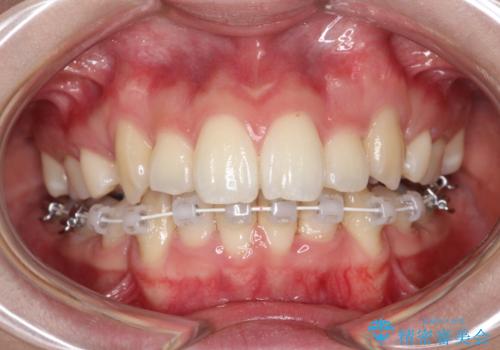

- ハーフリンガル

目立たない装置をご希望でしたので、上下左右の歯を1本ずつ抜歯してハーフリンガルでの矯正を行いました。